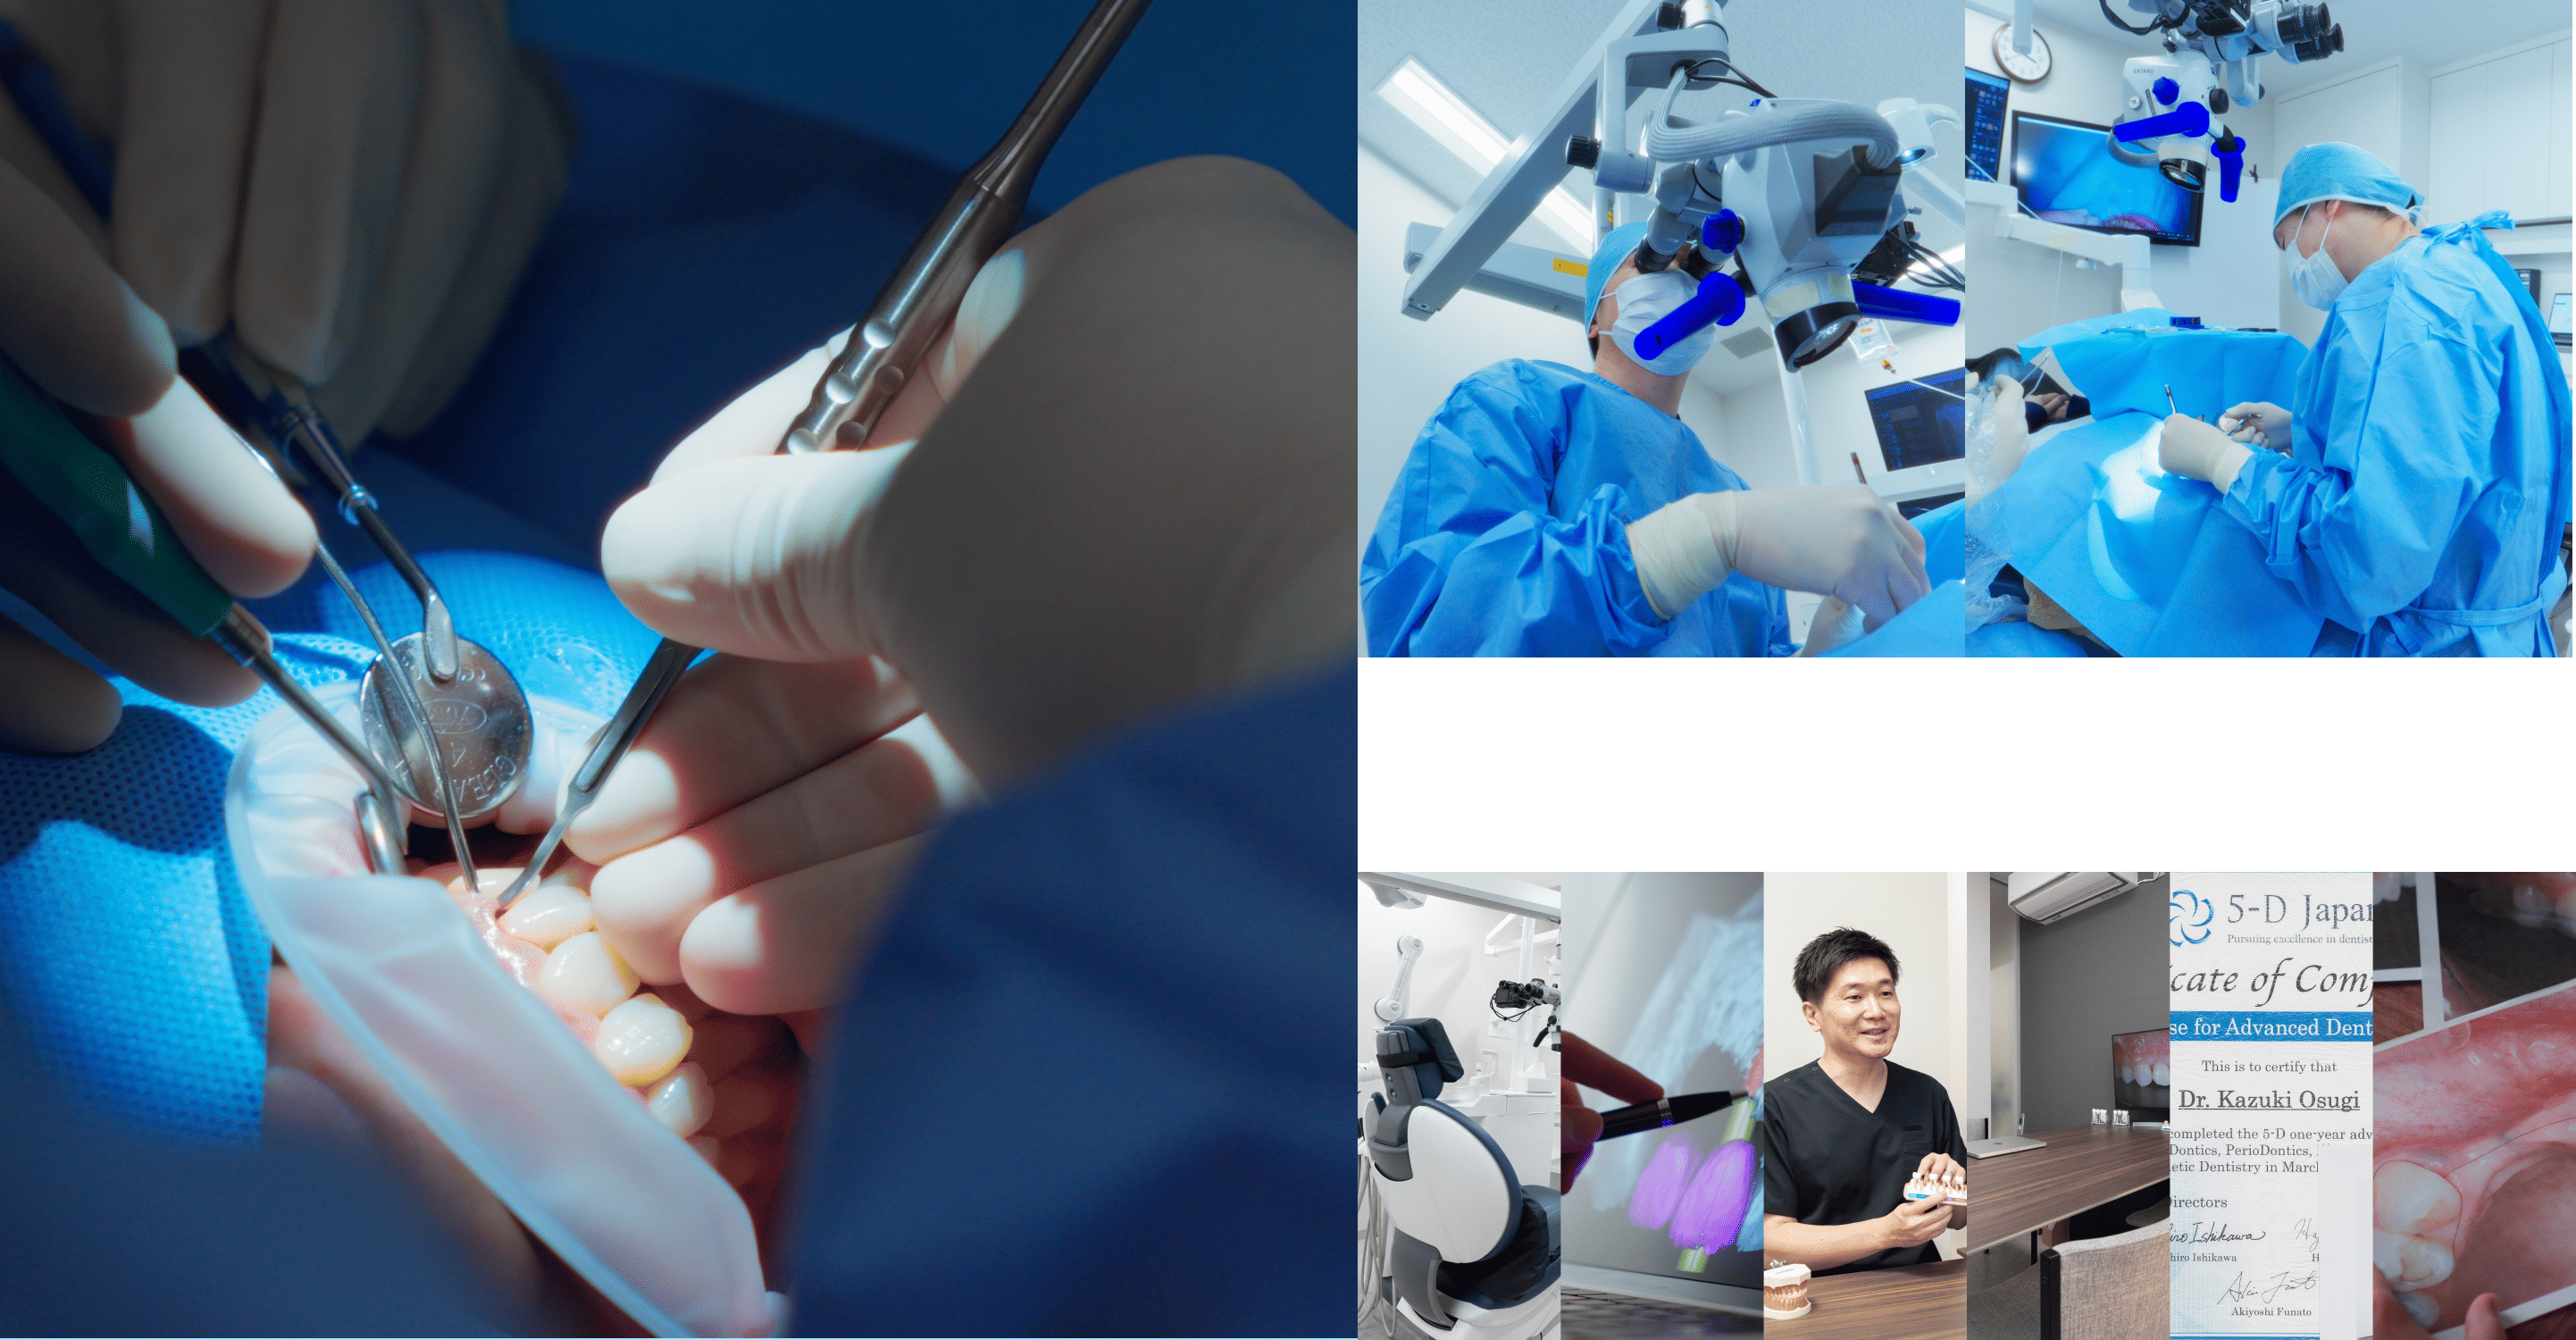

代表的な再生療法のひとつが「GBR(骨誘導再生法)」です。骨が不足した部位に自家骨や人工骨を補填し、特殊な膜(メンブレン)で覆うことで、骨の再生を促しインプラントの土台を築く方法です。

また、上顎奥歯など骨が特に薄い部位には「サイナスリフト(上顎洞底挙上術)」が適応されます。上顎洞と呼ばれる空洞の底を持ち上げ、その下に骨を造成することで、十分なインプラント埋入スペースを確保することが可能になります。

これらの高度な再生治療は、歯科用CTや精密シミュレーション技術、そして確かな経験を持つ術者による対応が前提となります。

これは、虫歯や歯周病などで抜歯が必要になった際、その当日にインプラントを埋め込む方法です。従来であれば、抜歯後に歯ぐきや骨の治癒を数ヶ月待ったうえで次のステップへ進んでいましたが、この方法を用いることで、治療期間を短縮できるほか、手術の回数も抑えられます。